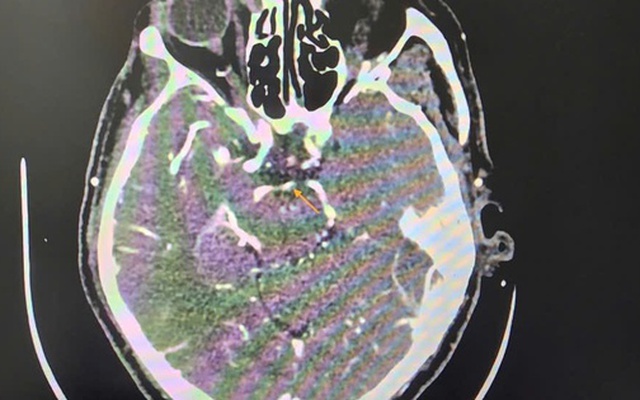

Đột quỵ khi uống bia, người đàn ông thoát chết ngoạn mục

Sống khỏe 2025-10-30T07:11:00Uống bia xong thấy chóng mặt, người đàn ông 60 tuổi bất ngờ bị đột quỵ thể nặng, được bác sĩ cứu sống ngoạn mục trong “thời gian vàng”.